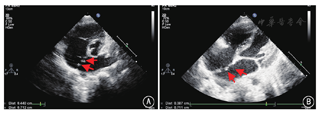

2016年4至8月在中国医学科学院阜外医院心脏外科门诊接受经胸超声心动图检查,满足以下条件的ASD患者入选本研究:(1)缺损数量>2个;(2)累计缺损直径≥5 mm;(3)年龄≥2岁。排除标准:(1)原发孔型ASD及静脉窦型ASD;(2)心内膜炎及出血性疾患;(3)封堵器安置处有血栓存在,导管插入处有静脉血栓形成;(4)严重肺动脉高压导致右向左分流;(5)左室射血分数<50%;(6)合并需外科处理的其他心脏畸形。封堵成功标准:封堵器稳定、形态正常、未压迫重要组织,无恶性心律失常,残余分流≤4 mm。所有患者入院后由同一名超声科医师重新进行超声检查,明确缺损数量、大小及缺损间距离(图1)。2016年4至8月,经超声检查初筛排除不适宜行封堵治疗的病例后,共入选21例患者,其中男8例,女13例,年龄3~48(20.33±16.64)岁,体重14~68(39.64±19.71)kg。本研究通过中国注册临床试验伦理审查委员会审批(ChiECRCT-2013036),所有患者均签署知情同意书。